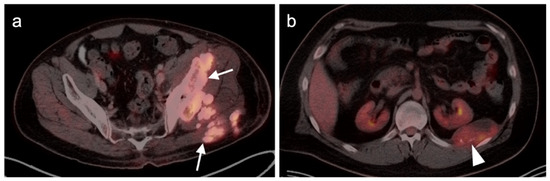

- Gao, Y.-J.; Yang, Z.; Yu, J.-Y.; Li, N.; Wang, X.-J.; Zhou, N.-N. Potential application value of PET/computed tomography in retroperitoneal leiomyosarcoma and a literature review. Nucl. Med. Commun. 2021, 42, 800–810. [Google Scholar] [CrossRef]

- Subramaniam, S.; Callahan, J.; Bressel, M.; Hofman, M.S.; Mitchell, C.; Hendry, S.; Vissers, F.L.; Van der Hiel, B.; Patel, D.; Van Houdt, W.J.; et al. The role of 18 F-FDG PET/CT in retroperitoneal sarcomas—A multicenter retrospective study. J. Surg. Oncol. 2021, 123, 1081–1087. [Google Scholar] [CrossRef]